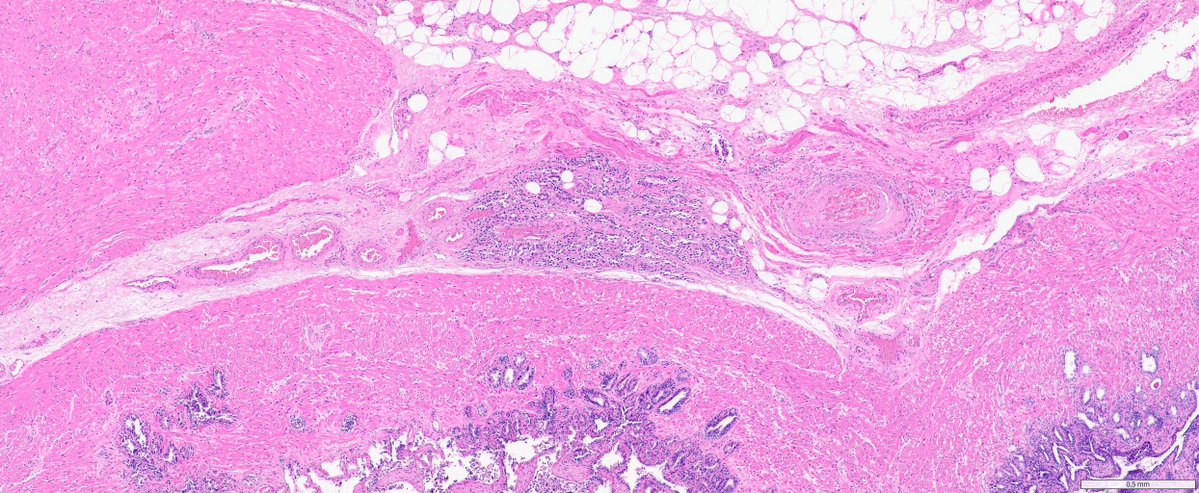

Brave New World of Breast Pathology 🧑🏫

HER2 interpretation is increasingly complex—with evolving definitions come real challenges, especially reproducibility. We’ll cover navigating HER2-low & ultralow in a clinically meaningful way.